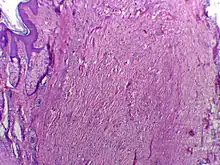

Micrographie de chéloïde. Les fibres épaisses de collagène sont caractéristiques de ce processus de cicatrisation aberrante. Coloration à l’hématoxyline et à l’éosine.